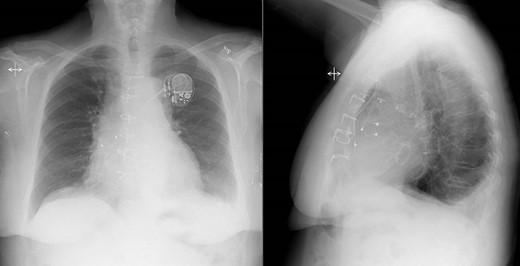

After spending 3 days on the thoracic intensive care unit, the patient was transferred to the surgical ward to continue intravenous antibiotic therapy. The postoperative course was uneventful and on the seventh postoperative day, a pacemaker generator was connected to the tunneled electrodes. Routine postoperative echocardiogram confirmed the perioperative findings with well-functioning biological prostheses in aortic and mitral positions. Postoperative chest X-ray also showed ordinary findings (Fig. 3). Cultures from the native mitral valve and the TAVR prosthesis were positive for Cutibacterium spp. Initially, the patient was treated with a combination of Vancomycin and Cefotaxime. Cefotaxime was withdrawn after 2 weeks and Vancomycin in single therapy was continued another 2 weeks, and the patient was discharged to her home after 4 weeks of postoperative intravenous antibiotic therapy. At discharge, she was feeling well with no fever, a CRP concentration of 13 mg/L and a leukocyte count of 5.0 x 109/L (reference 3.5–9.0 x 109/L).

Postoperative chest X-ray showed ordinary findings with only a small amount of bilateral pleural effusion and adjacent pulmonary atelectasis.